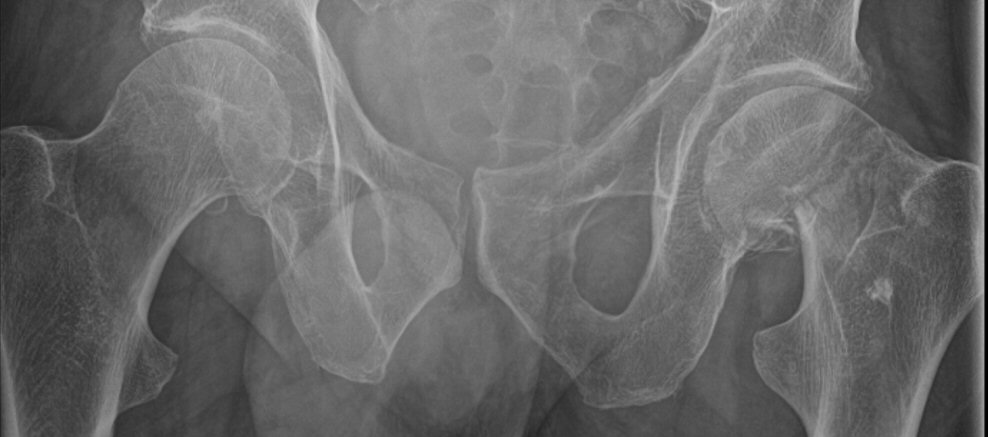

- Värdera om benet är rätt (ska vara 15° inåt) och sidlikt roterade. Trokanter minor bör vara symmetriska på vänster och höger sida. Vid fraktur så brukar det frakturerade benet vara utåtroterat.

- Värdera om röntgenbilden är tagen rakt framifrån. I så fall bör coccyx och symfysen ligga över varandra och foramina obturatoria bör vara symmetriska.

Första bilden är nästan rak frontal med överlappande coccyx och symfys samt symmetriska foramina obturatoria. Andra bilden är inte rak.